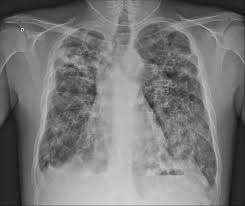

Human chest bone structure parts of the chest bones. Thoracic cavity, also called chest cavity, the second largest hollow space of the body.it is enclosed by the ribs, the vertebral column, and the sternum, or breastbone, and is separated from the abdominal cavity (the body's largest hollow space) by a muscular and membranous partition, the diaphragm.it contains the lungs, the middle and lower airways—the tracheobronchial tree—the heart. A chest radiograph in isolation is limited in its contribution to diagnosis, and its usefulness is enhanced right neck paratracheal area aortic arch right hilum left hilum vascular shadows (aorta; Find out from webmd about other health problems that could be to blame. The abdominal cavity is the part of the body that houses the stomach, liver, pancreas, kidneys, gallbladder, spleen, and the large and small intestines.the diaphragm marks the top of the abdomen and the horizontal line at the level of the top of the pelvis marks the bottom.